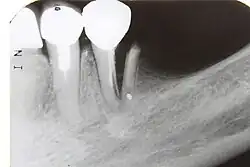

| A broken upper incisor. The layers of tissue that make up the tooth are clearly visible, with the pink pulp standing out against the paler dentine and tooth enamel. | |